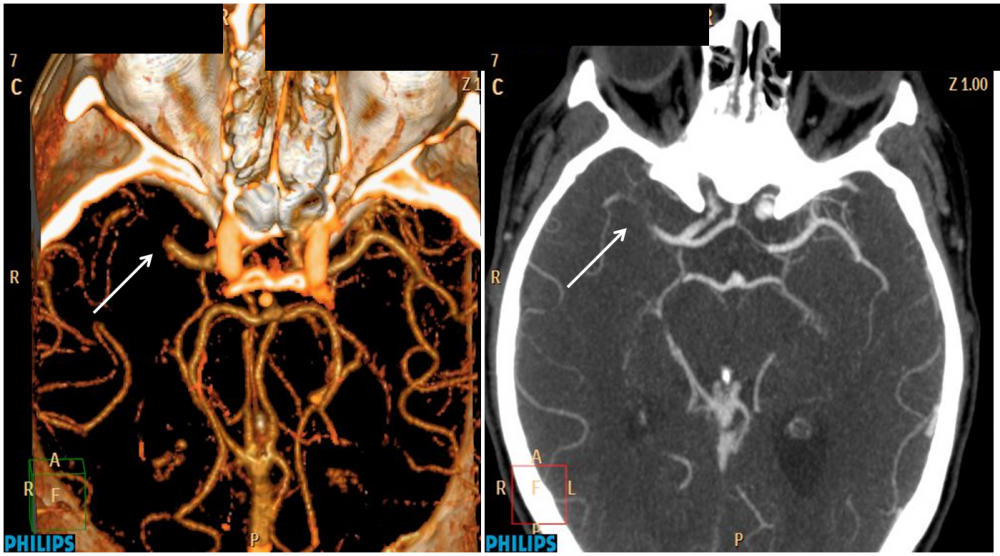

•Huesos | Tejido Blando | Vasos Sanguíneos | Órganos Internos

• Inflamaciones | Aneurismas | Tumores | Cáncer

Ejemplo de Imagen informativa